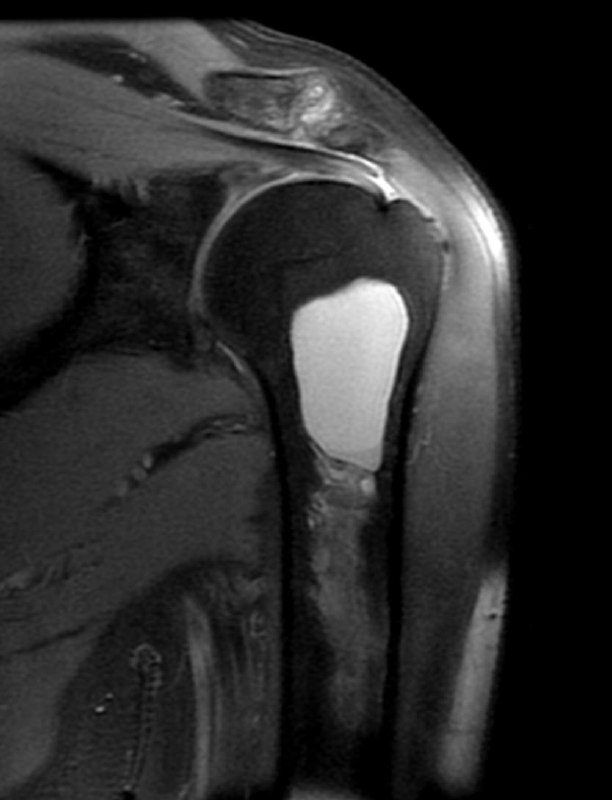

показательный случай острого (хорошо, свежего!) разрыва сухожилия длинной головки бицепса плеча, с приличным диастазом. стрелками указаны края дистального и проксимального фрагментов сухожилия. На последнем снимке - пустая межбугорковая борозда